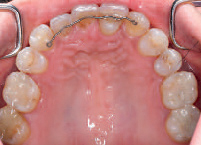

- 17. Frontaal aanzicht van de 25 en de naar mesiaal verplaatste 13.

- 18. Dezelfde situatie vanaf occlusaal.